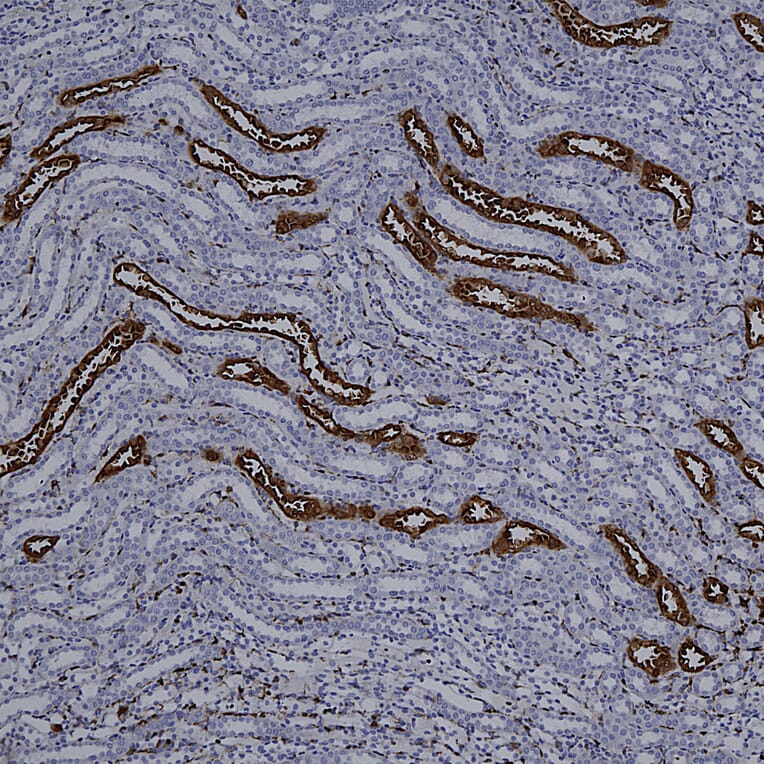

Immunohistochemistry analysis of a 4% PFA fixed paraffin embedded rat kidney section with Anti-Galectin 3 Antibody [5C21] (A85368) at a dilution of 1:1,000 detected with DAB (brown) using the Vector Labs ImmPRESS method and reagents with citra buffer retrieval. Counterstained with Hematoxylin (blue). In kidney, the Anti-Galectin 3 Antibody [5C21] (A85368) strongly and specifically labels collecting ducts and distal tubules. Note: this antibody performs well in testing with both 4% PFA and standard NBF fixed, rat and human tissues.